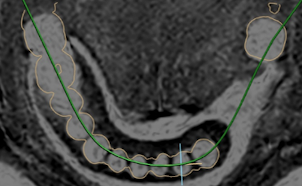

Parodontitis ist eine weit verbreitete Volkskrankheit, welche unentdeckt häufig zu Zahnverlust führt.

Durch MRT können bereits sehr frühe Krankheitsstadien sichtbar gemacht werden, noch bevor es zum Knochenverlust gekommen ist. Etablierte, röntgenbasierte Verfahren erfassen lediglich den bereits stattgehabten Knochenabbau, was einem spätem, oft irreversiblem Stadium entspricht. Durch MRT kann die Erkrankung des Zahnhalteapparates zudem verlaufskontrolliert werden, da die strahlenfreien Untersuchungen im Verlauf beliebig wiederholt werden können.